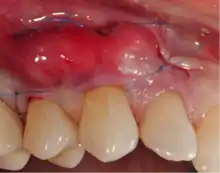

Exposure of the tooth root due to loss of keratinized tissue around the neck of a tooth is referred to as gingival recession. This can result in sensitivity or pain from the exposed tooth root surface (dentin is more permeable and soft compared to enamel and dentin is what makes up the tooth root).[7] Recession may also cause an unasthetic appearance especially if located in the anterior dentition (front teeth). While not all cases of gingival recession require surgical correction, there are various options if that is what the patient desires.[8] It should be reinforced that recession left untreated will not result in tooth loss, contrary to popular belief. Also, recession that is left untreated can be maintained and the inflammation kept at bay with proper brushing and oral hygiene technique.[5] On the other hand, if one desires to pursue corrective therapy, there are a wide variety of techniques ranging from autograft (your own tissue, usually taken from the palate), allograft (someone else's tissue, cadaver), xenograft (animal, usually porcine or bovine) or simply repositioning of the tissue native to the site.[9] The benefits of corrective therapy often result in decreased sensitivity through coverage of the root surface in addition to a gain in the keratinized tissue mentioned beforehand.

Gum grafting, also known as a gingival graft or periodontal plastic surgery, is a surgical procedure to reverse gum recession. Gum recession exposes the roots of teeth,[10] which can lead to sensitivity and put teeth at a higher risk of damage or disease[11] due to the loosening of their attachment within the gums and bones of the jaw. Should gum recession continue, bone and keratinized tissue will be at greater risk of being damaged and permanently lost around the teeth. The aim of a gum graft is to extend keratinized tissue of the gums to cover tooth roots,[12] which restores their firm placement within the jaw and prevents further damage.